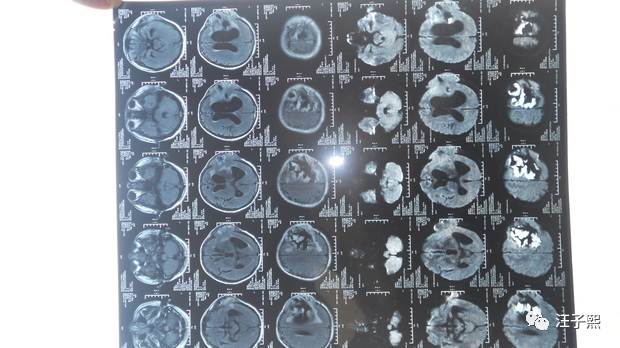

Jerry之前的文章 记一次SAP开发工程师给微软Azure报incident的体验,也提到自己处理incident和给别的程序员报incident的经历,没想到,这次有医生给我身上这台生物系统报了incident,而且priority还是very high的。一个专业的程序员,在接到incident之后,都是从“问题重现-问题定位-设计解决方案-处理问题-测试”这几个步骤进行的。我最近,凭着Google和金山词霸,也在看相关的英文论文,从病的诱因,诊断,治疗和预后这几个方面来学习,恶补了一大堆理论知识,虽然对我实际可能没什么用,甚至会让我的情绪变得消极,然而我的这些行为都是一个程序员的职业习惯使然——不管遇到什么问题都想刨根究底。